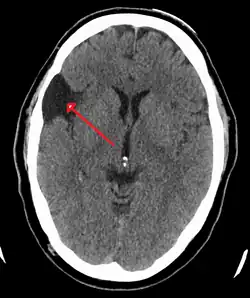

.jpg) | |

| An MRI of a 25-year-old woman with left frontotemporal arachnoid cyst. | |